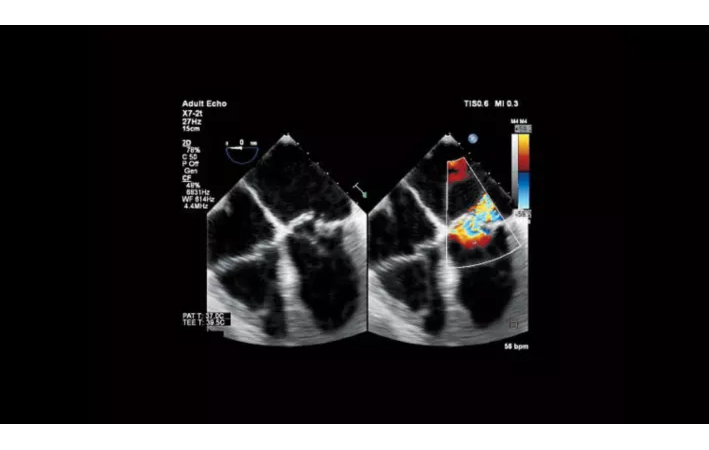

Более точная клиническая информация о жесткости тканей

Affiniti 50 поддерживает высокочувствительную компрессионную эластографию, которая не требует внешней компрессии и может использоваться для оценки относительной жесткости различных тканей, включая малые органы, молочные железы и гинекологию.

- Компрессионная эластография для молочной железы и органов малого таза

Исследования в онкологии

Strain Elastography - эластография